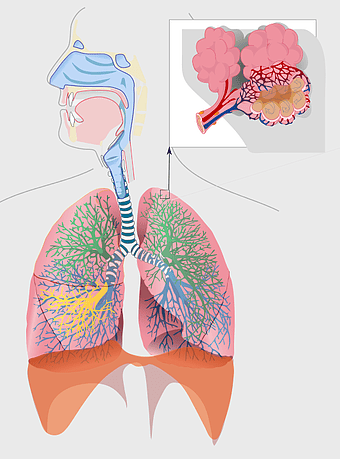

Respiratory system diagram, bronchiole structure, lung anatomy illustration, pulmonary alveolus function, respiratory health, breathing process visualization, trachea pathway -

Human Respiratory System illustration, pulmonary anatomy, trachea structure, respiratory organ function, bronchial tree, alveoli exchange, thoracic cavity -